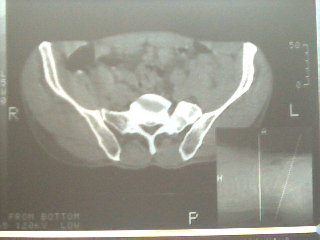

以下是引用sdqzwyx在2006-12-6 13:22:00的发言:[br]图片不全,考虑腰5不完全骶化(腰5左侧横突肥大与骶骨形成关节),定位像应该很明确的。

以下是引用乡医在2006-12-6 14:55:00的发言:[br]腰5左侧横突肥大,属发育变异。

以下是引用一棵树在2006-12-6 13:13:00的发言:[br]腰5左侧横突肥大(比较常见)